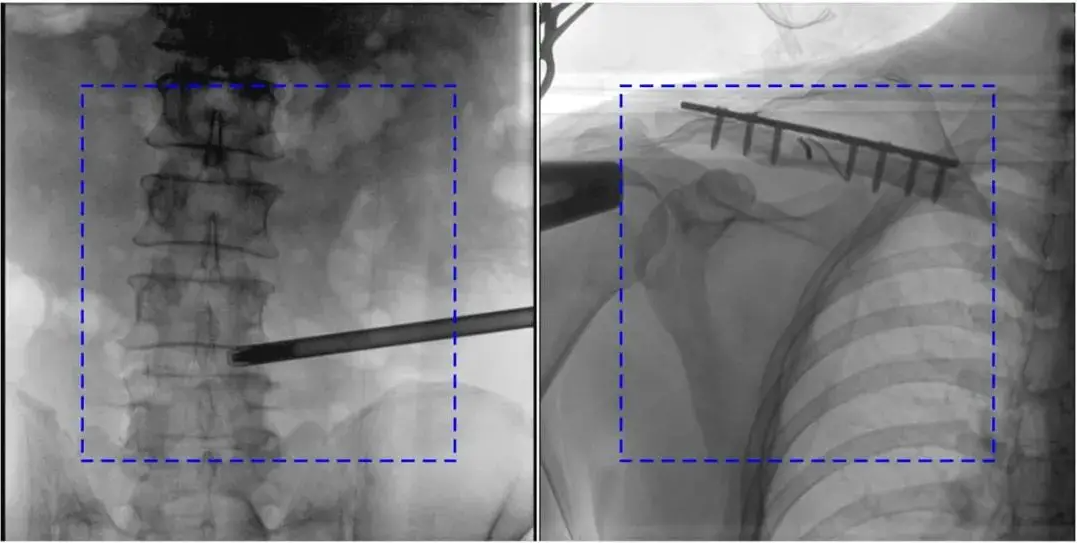

C臂机作为骨科手术和介入治疗的核心影像设备,其图像质量直接影响临床诊断的准确性。医院在使用C臂机时,如果遇到图像不清楚的情况,多半是有以下这些原因导致的(附解决办法)。

AEC模式下,金属植入物或患者体位偏离视野中心可能导致曝光不足或过度。

解决办法:手动调整曝光参数,确保感兴趣区域位于视野中央;避免金属干扰,必要时调整患者体位。